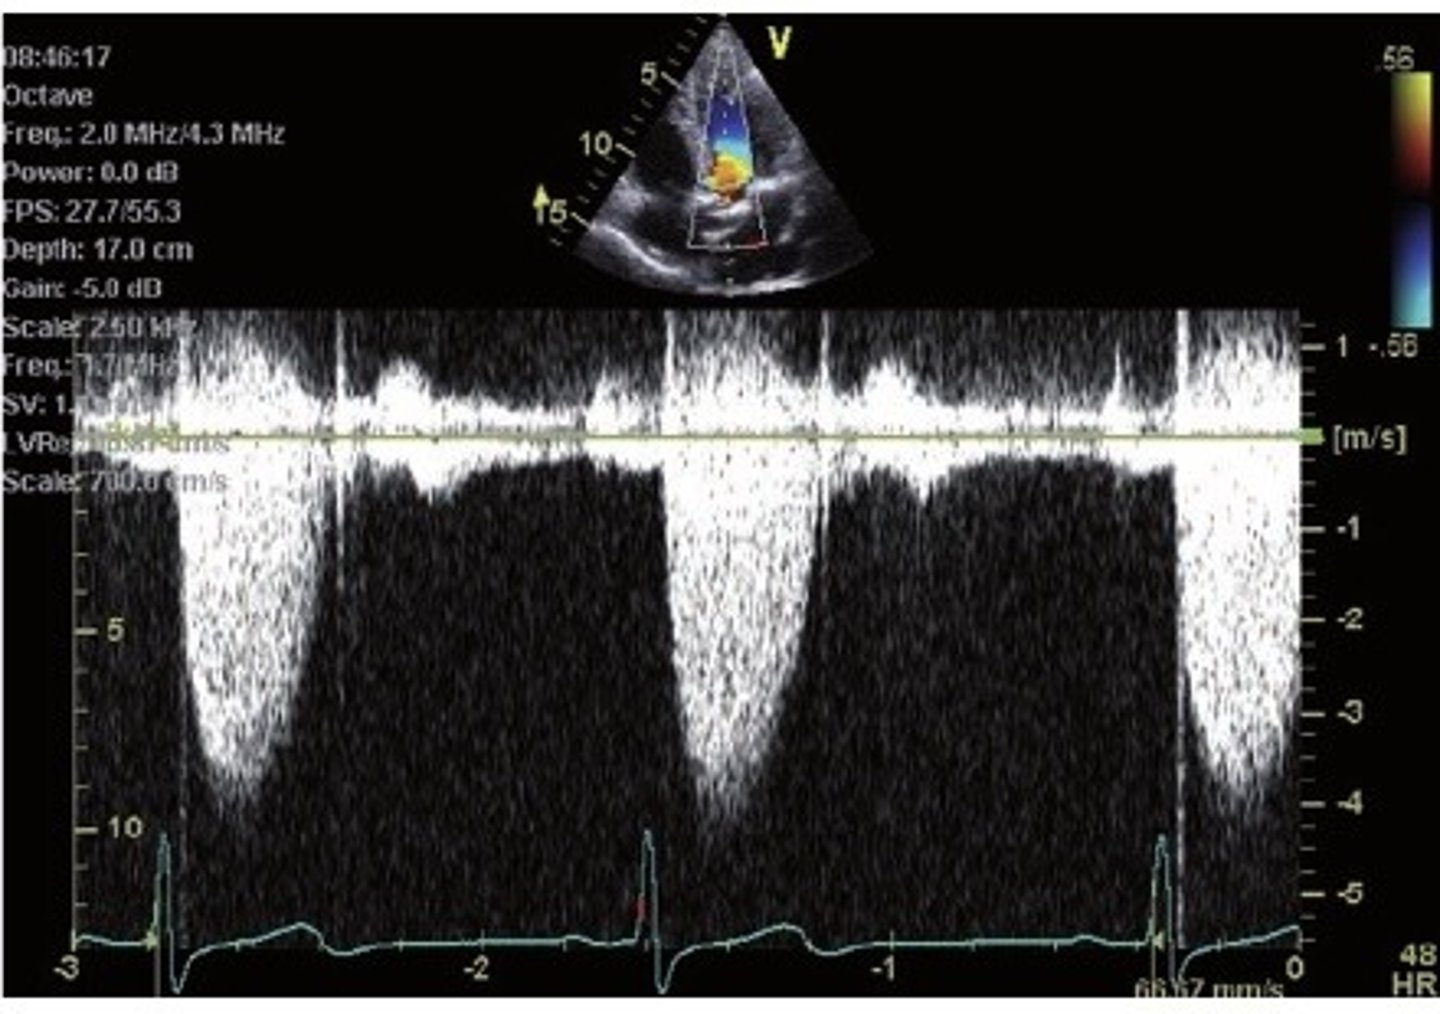

velocity vs time: flow toward probe appears above graph baseline, flow away appears below baseline

What does the quantitive doppler graph indicate? What do the waves show?

continuous wave doppler, the peaks are filled

which type of quantitative doppler is this? How can you tell?